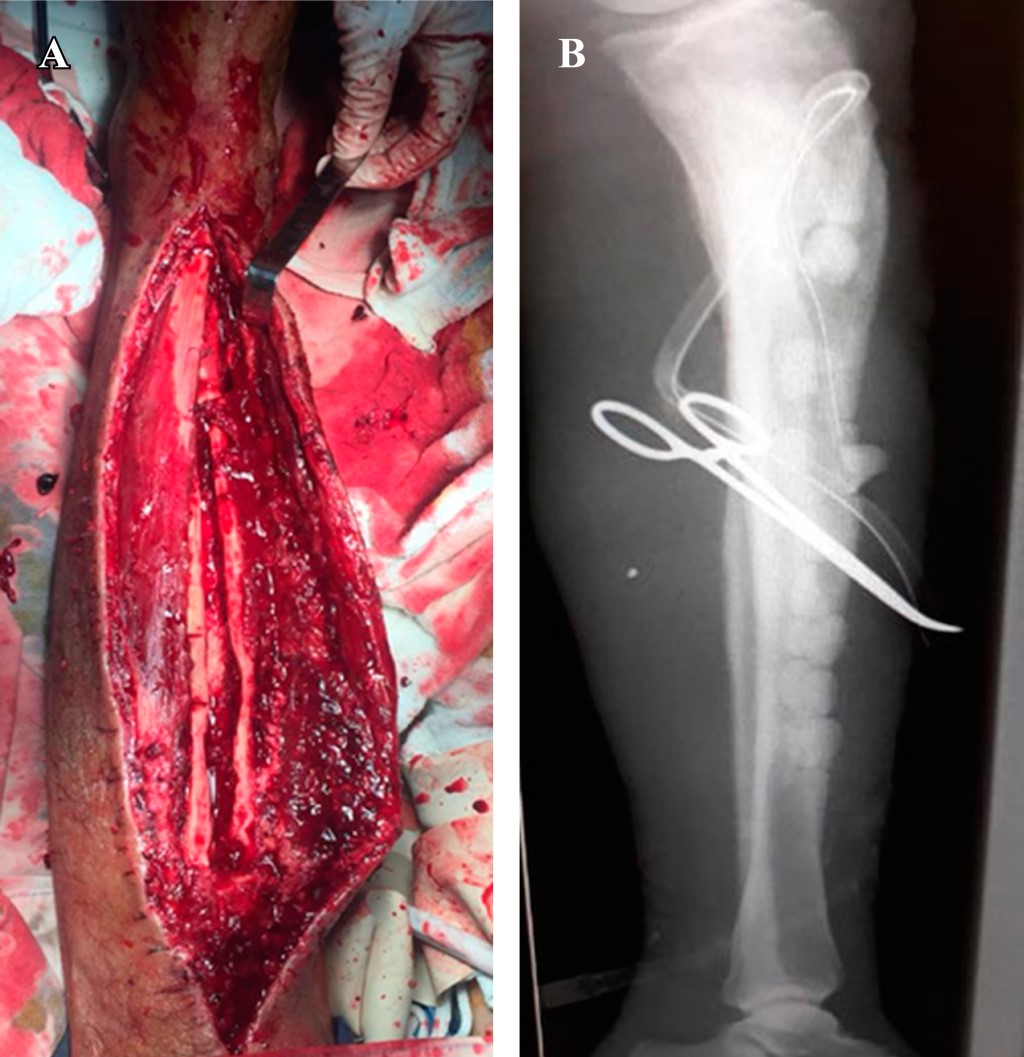

En el primer tiempo se realiza hemidiafisectomía lineal anterior desde región proximal a nivel metafisario con resección de tejido óseo secuestrado hasta región de tuberosidad tibial anterior, evacuación medular de dicha región anatómica obteniendo secreción de coloración amarillenta fétida abundante, se efectúa escarificación de canal medular hasta obtener tejido óseo sangrante, se colocan perlas de cemento medicado con amikacina en cavidad medular y sistema endomedular de osteoclisis para irrigación con solución fisiológica 100 ml más un 1 g de vancomicina cada 24 horas por 10 días (Figura 2).

Figura 2